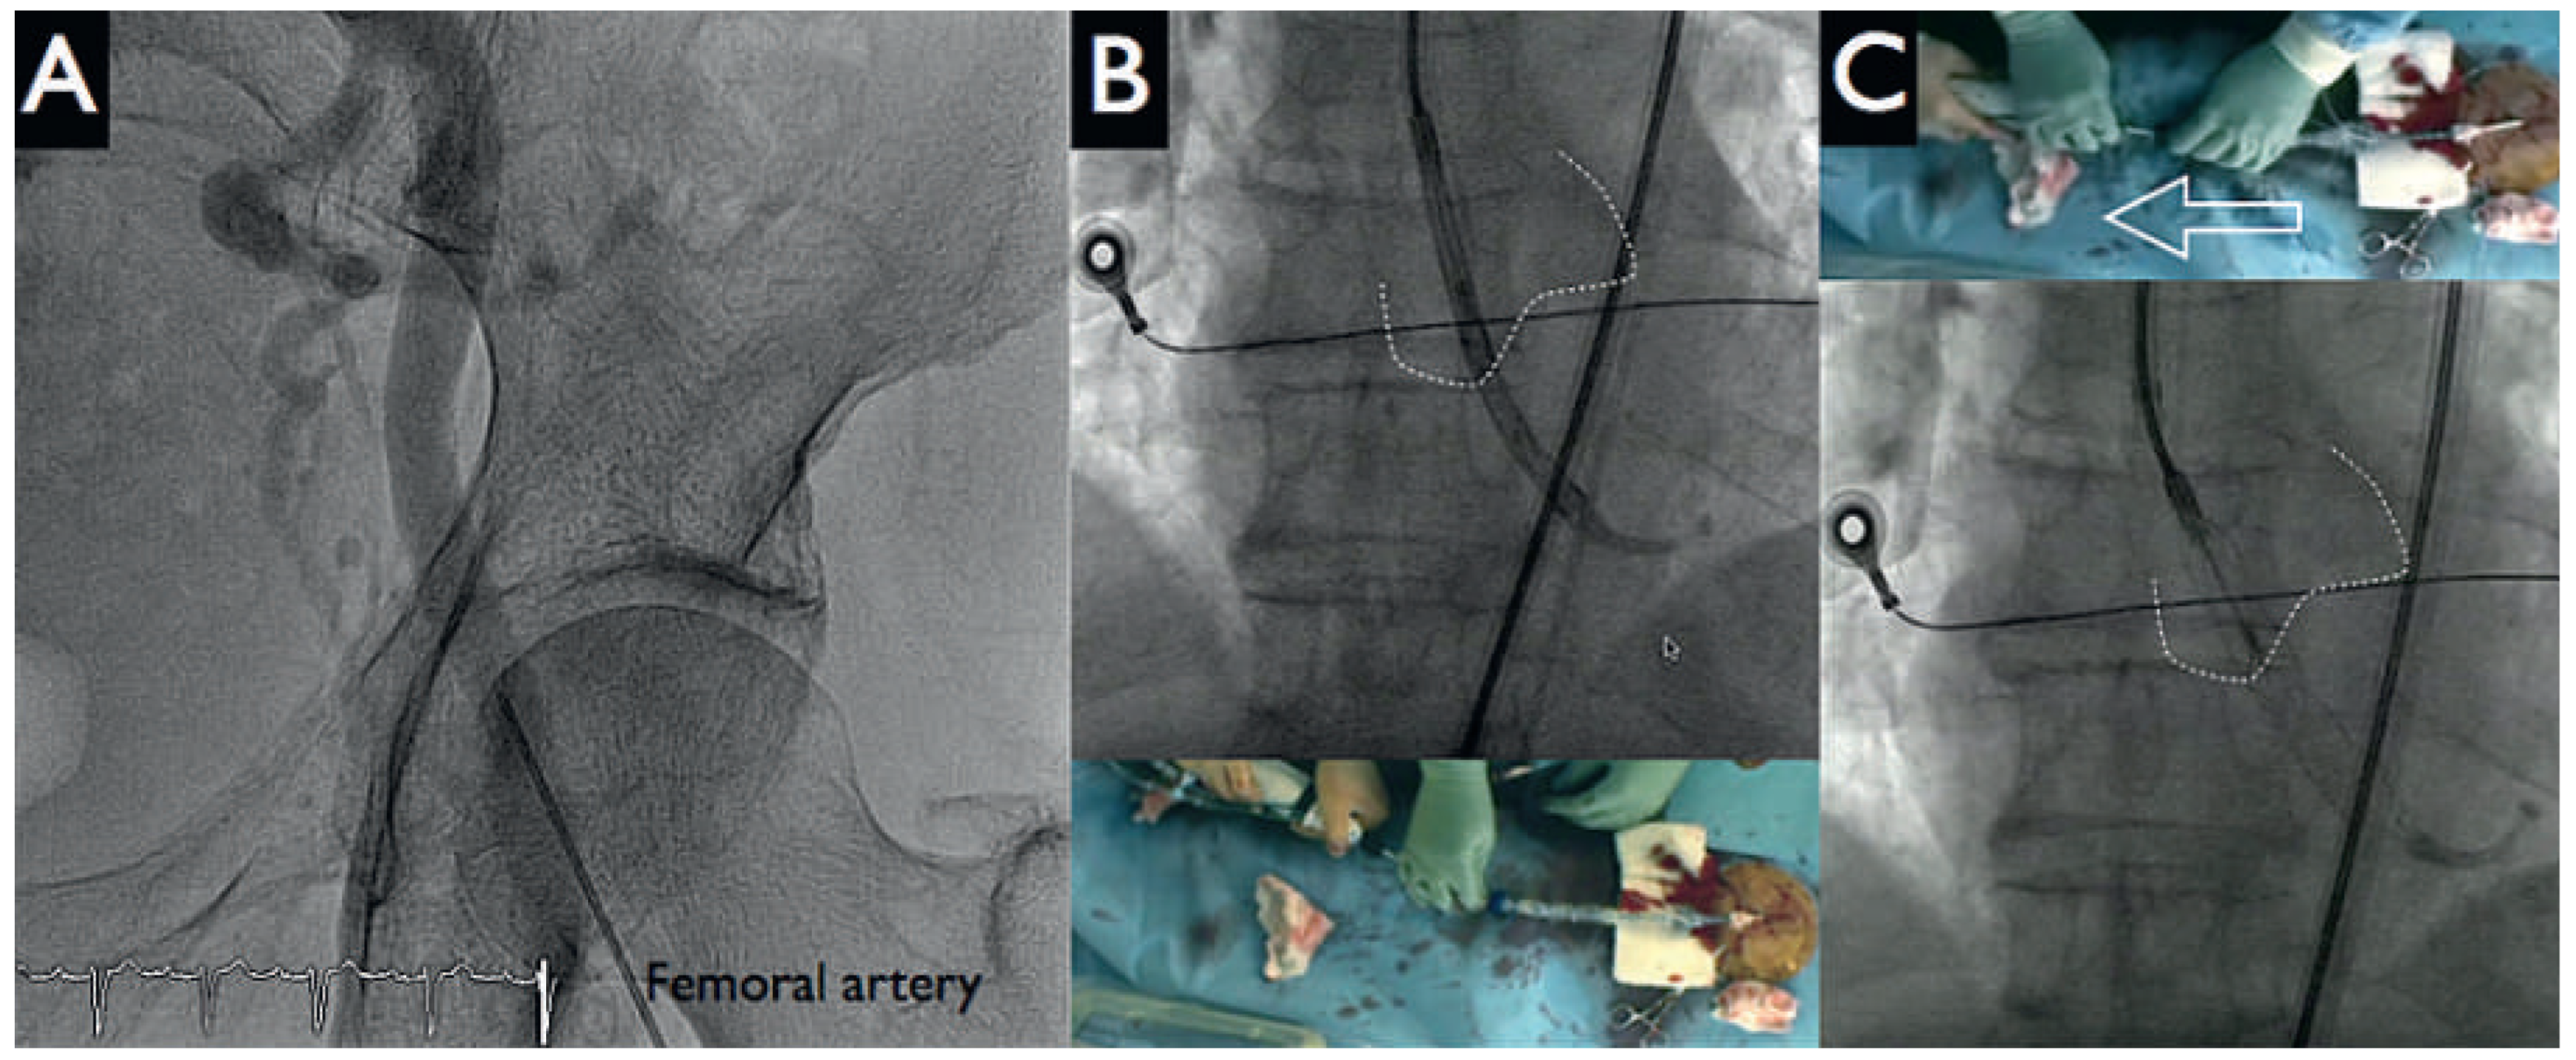

An otherwise active and independent 86-year-old male with a history of poorly controlled hypertension consulted for progressive shortness of breath and typical angina Canadian Cardiovascular Society (CCS) class III. His ECG showed first degree atrioventricular block, a left anterior hemiblock and Q waves from V1–V4. There was left ventricular hypertrophy with severe systolic dysfunction (left ventricular ejection fratction [LVEF] 30%) and anterior wall hypokinesis, but no significant valvular disease on echocardiogram (left ventricular angiogram, Figure 2 panels E, F). The coronary angiogram revealed severe three-vessel coronary artery disease (Figure 2 panels A–D). There was a significant stenosis of the distal left main (Medina 1.1.1). The left anterior descending artery was suboccluded in the proximal and distal portion with numerous calcified and aneurysmal lesions. The proximal, middle and distal circumflex artery, as well as the mid portion of the right coronary artery, had significant stenosis.

Figure 2. Coronary angiograms (panels A–D) and left ventricular angiogram (panels E, F). Three-vessel coronary artery disease with subtotal distal left main (3) to proximal left anterior descending artery (LAD) stenosis (lesion 1), significant proximal (lesion 2) and distal (lesion 3) LAD stenosis, high grade ostial circumflex artery (LCx, lesion 4), and intermediate lesions from the mid portions of LCx and the right coronary artery (RCA). Left ventricular ejection fraction was severely depressed (panels E, F).